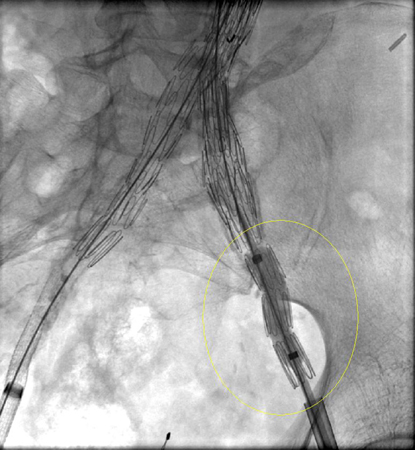

Endofuga tipo I en anastomosis distal de la ilíaca izquierda (fuga marcada con un círculo)

University of Michigan, específicamente los casos del Dr. Upchurch que reflejan los Departamentos de Cirugía Vascular y Radiología

Extensión de endoprótesis expandida para la misma endofuga tipo I (marcada con un círculo)